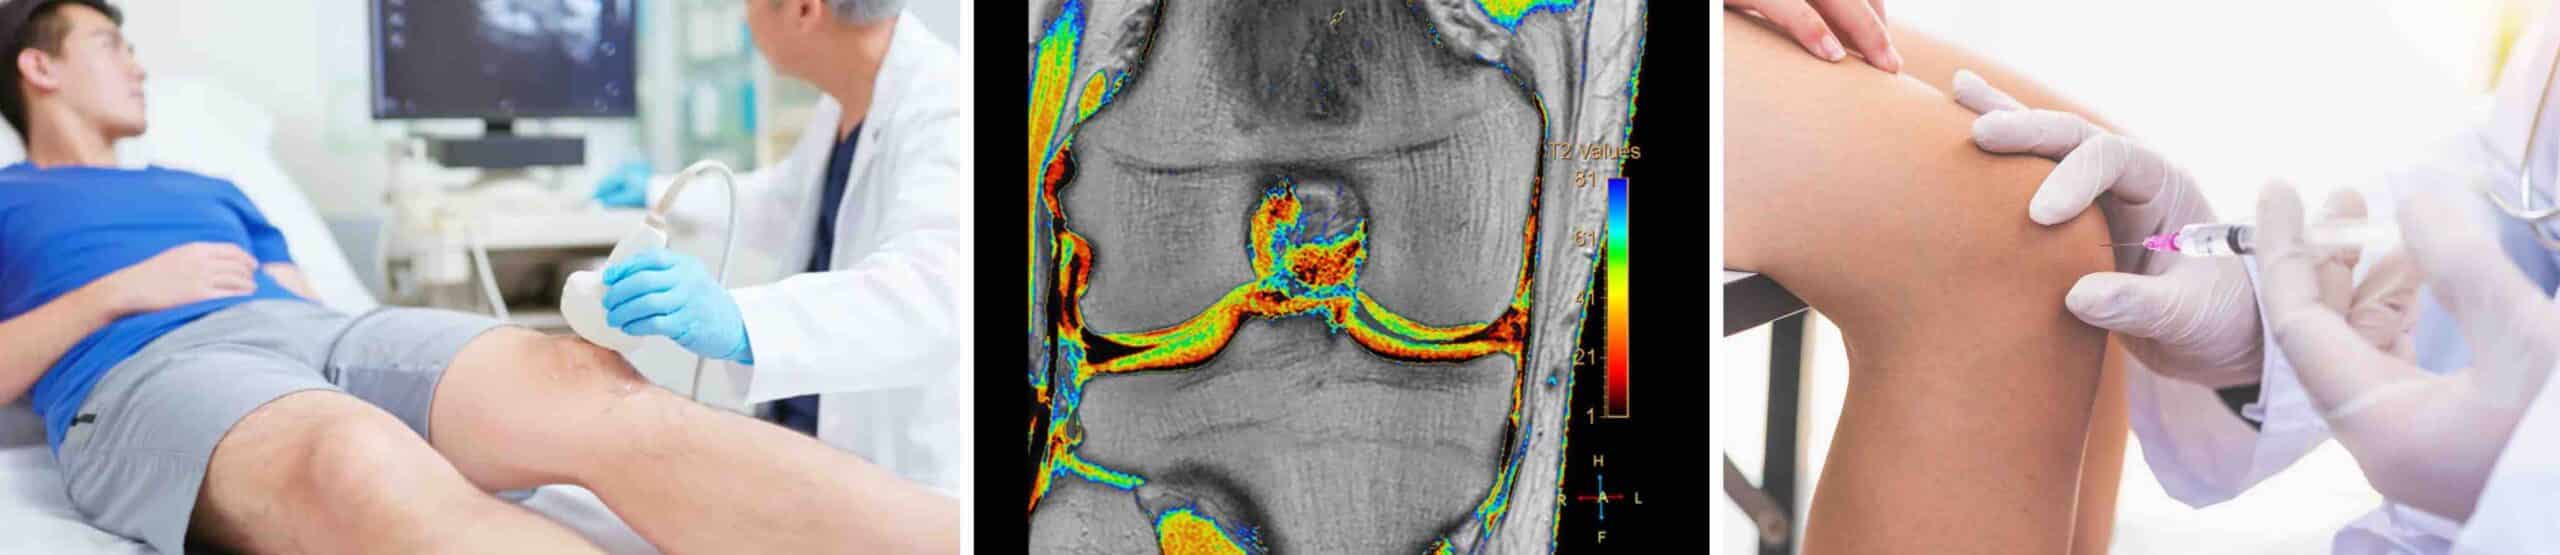

A injeção antienvelhecimento para o joelho com os melhores resultados clínicos na atualidade é a viscossuplementação com ácido hialurônico. O envelhecimento é um processo natural, mas a forma como ele afeta as articulações do nosso corpo pode variar drasticamente entre diferentes indivíduos. Para muitas pessoas, a percepção de que a “idade está chegando” se manifesta primeiro nos joelhos. Rangidos, dor para subir e descer escadas, agachar e ajoelhar, além de rigidez matinal, são os primeiros sintomas de comprometimento da cartilagem do joelho. No entanto, a medicina evoluiu bastante a ponto de oferecer uma solução que funciona como uma verdadeira “injeção antienvelhecimento para o joelho”: a viscossuplementação com ácido hialurônico.

O envelhecimento é um processo biológico complexo, progressivo e irreversível, caracterizado pela perda gradual da capacidade funcional e da eficiência de reparo do organismo. Para muitas pessoas o envelhecimento se manifesta inicialmente nos joelhos. O joelho é a maior e mais complexa articulação do nosso corpo. Por suportar o peso do corpo, pequenas mudanças estruturais, como as que são causadas pelo processo de envelhecer, podem causar sintomas importantes. O envelhecimento do joelho, tecnicamente conhecido como degeneração articular, é um processo degenerativo onde a cartilagem perde sua espessura, elasticidade e capacidade de retenção de água, resultando em maior atrito direto entre os ossos que se articulam. Esse desgaste da cartilagem, conhecido como artrose, é frequentemente acompanhado pela redução da qualidade do líquido sinovial, o lubrificante natural da articulação, o que gera sintomas como rigidez, estalos, rangidos e dor crônica. A intervenção precoce, quando os primeiros sintomas de comprometimento da cartilagem aparecem, pode preservar a função e a mobilidade articular.

O ácido hialurônico é uma substância naturalmente presente no nosso organismo, especialmente no líquido sinovial, que é o líquido lubrificante das nossas articulações. O líquido sinovial tem alta viscosidade por causa da presença de ácido hialurônico na sua composição. Com o passar dos anos, ou devido a lesões ou desgastes precoces da cartilagem, a concentração e a qualidade do ácido hialurônico no líquido sinovial do joelho diminuem, deixando a cartilagem desidratada e exposta a atrito direto. A injeção antienvelhecimento para o joelho, ou viscossuplementação, é a aplicação intra-articular de ácido hialurônico para melhorar a qualidade e a viscosidade do líquido sinovial. É como “trocar o óleo” de uma engrenagem que está trabalhando a seco, devolvendo a viscosidade e a proteção necessárias para o movimento fluido articular.

Os benefícios da aplicação de ácido hialurônico no joelho são excepcionais para a cartilagem, ajudando na preservação da saúde articular a longo prazo. Os principais benefícios são: lubrificação mecânica da cartilagem, ação anti-inflamatória intra-articular, estímulo à produção endógena de ácido hialurônico, hidratação da cartilagem e a prorrogação, ou até mesmo a prevenção, de uma intervenção cirúrgica agressiva como a cirurgia de prótese de joelho. Esses benefícios fazem com que a aplicação de ácido hialurônico no joelho funcione como um verdadeiro tratamento antienvelhecimento da articulação.

A aplicação de ácido hialurônico no joelho é indicada para todas as patologias que cursam com a degradação da cartilagem como condromalácia, artrose, lesões condrais e condropatias.

Pacientes com sintomas de problemas na cartilagem do joelho devem consultar um médico ortopedista especialista em joelho. Os melhores resultados da aplicação intra-articular no joelho de ácido hialurônico dependem de um fator crucial: o diagnóstico precoce da patologia condral. Muitas pessoas cometem o erro de ignorar os primeiros estalos, rangidos e dores leves, recorrendo à automedicação com analgésicos comuns. Isso apenas mascara o problema enquanto a cartilagem continua a se deteriorar. O grande problema é que a cartilagem não se regenera. O comprometimento condral é irreversível. Portanto, preservar a cartilagem que você ainda tem é a estratégia mais inteligente e isso é possível com a aplicação intra-articular no joelho de ácido hialurônico, a verdadeira injeção antienvelhecimento para o joelho. Consultar um médico especialista assim que os primeiros sintomas surgirem é fundamental para a precisão do diagnóstico, a indicação do tratamento e a escolha da combinação de medicamentos e suas dosagens, que são específicos para cada caso.